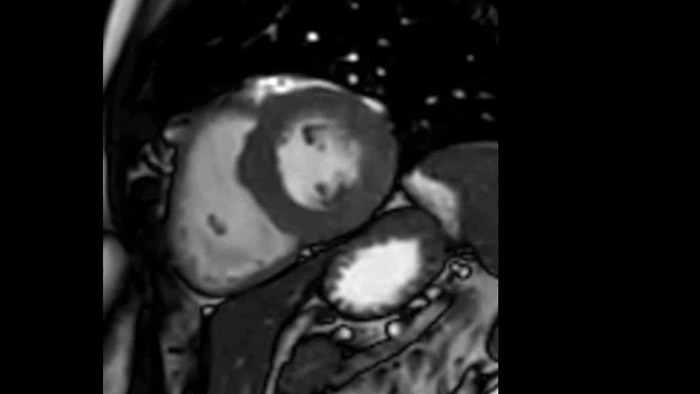

Diagnostic and prognostic utility of cardiac MR is increasing. Assess the anatomy and function of the heart using cine acquisitions, acquire information about perfusion and viability of the cardiac tissue, visualise potential edema with black blood sequence, access and even quantify tissue characterisation with CardiacQuant.

Due to the design of the BlueSeal magnet there is a negligible energy transfer from gradient coil to the magnet. This allows to maintain perfect B0 stability overtime which is especially beneficial for B0 sensitive acquisitions like cardiac bTFE sequences.